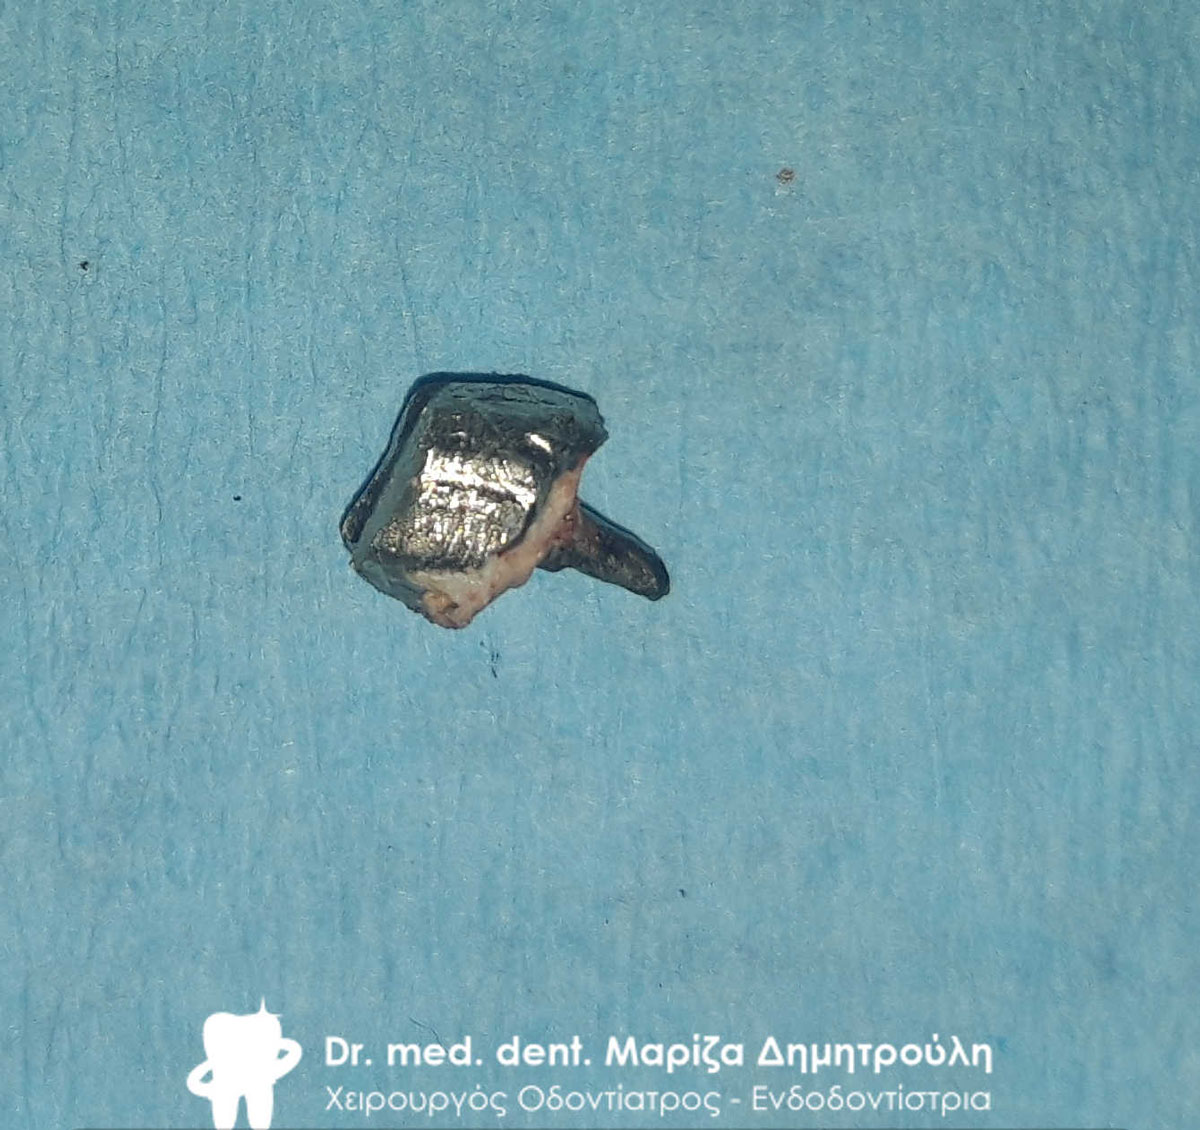

Μεταλλικός άξονας που αφαιρέθηκε πολύ προσεχτικά από τον δεύτερο γομφίο

Ο μεταλλικός άξονας που αφαιρέθηκε από τον τομέα με σκοπό να εκτιμηθεί το δόντι